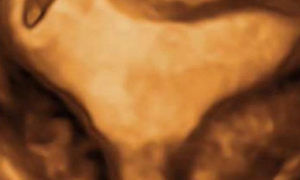

Leggi di piùCari soci, questo mese un nuovo video "How to do", sulla diagnosi ecografica di gravidanza su cicatrice di pregresso taglio cesareo. Grazie a Francesco Forlani! Il video è accessibile ai...